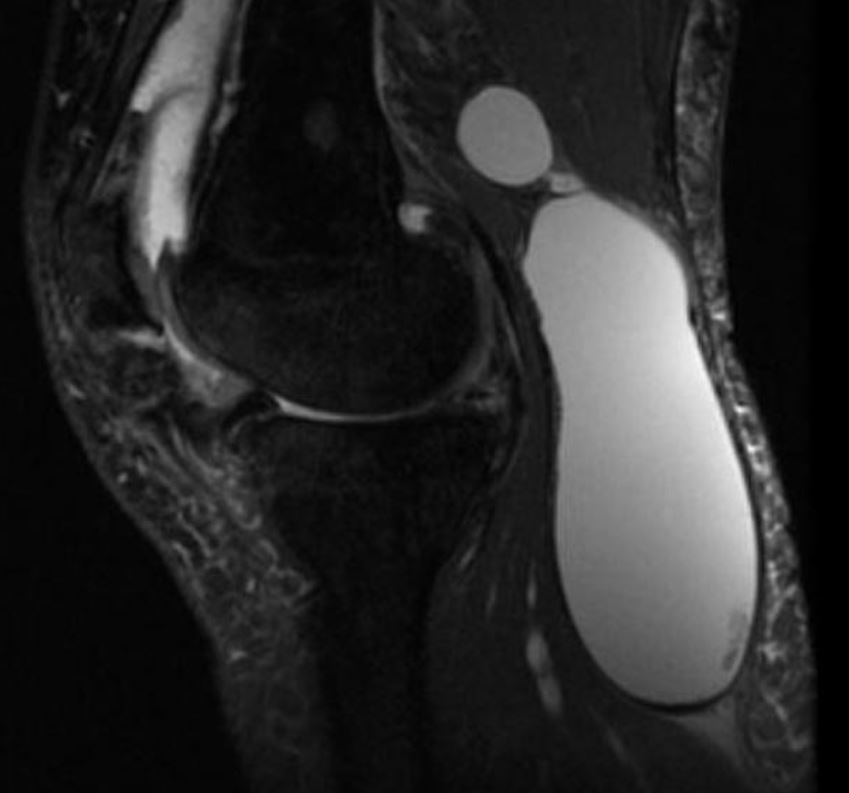

- назначает малышу МРТ, а также УЗИ.